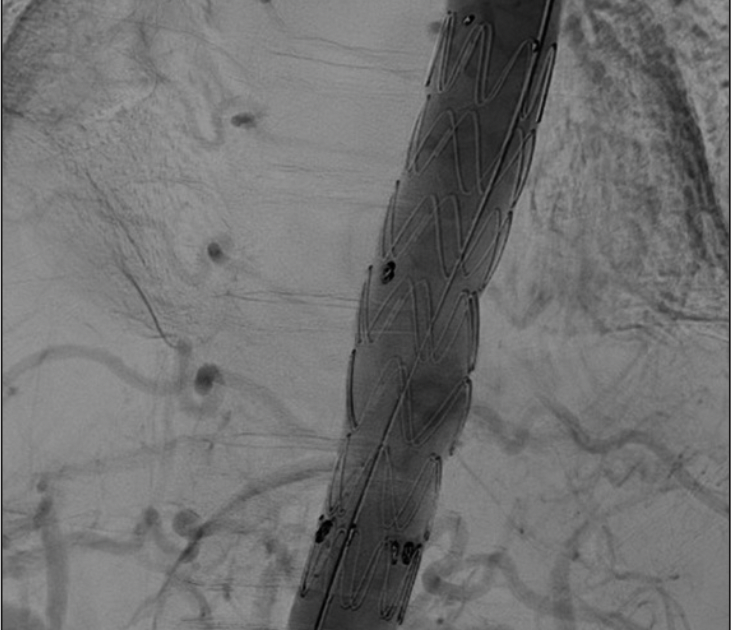

Manejo endovascular de hemoptisis secundaria a pseudoaneurisma de la aorta torácica, mediante un abordaje proximal.

Resultados: Se presenta el caso de paciente masculino, 56 años, que cursó con cuadro de hemoptisis, posteriormente objetivado como secundario a un pseudoaneurisma de la aorta torácica. Entre sus antecedentes destaca, enfermedad aorto-ilíaca tratada mediante un bypass de aorta torácica. Se decidió la reparación endovascular, mediante un abordaje proximal, utilizando la arteria axilar.

Discusión: Las indicaciones para el uso de la reparación  endovascular de la aorta torácica (TEVAR) se están expandiendo ampliamente, incluyendo a pacientes previamente intervenidos o aquellos que antiguamente se consideraban con un riesgo prohibitivamente alto para una cirugía. La fístula aorto-bronquial, es una complicación rara, sin embargo, existe correlación entre su desarrollo y la cirugía de aorta torácica.  La sospecha diagnóstica debe ser alta. El AngioTC, cumple un doble rol, siendo útil para el  diagnóstico, como para la planificación preoperatoria, hecho fundamental para lograr una terapia adecuada.